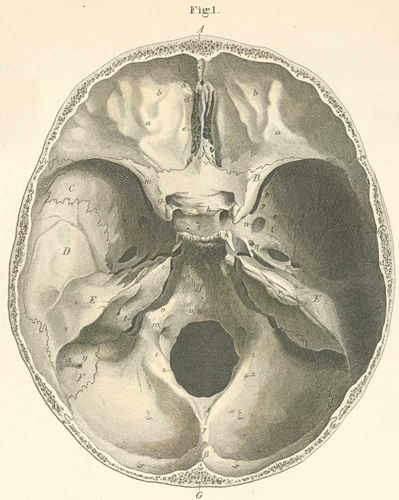

Skull base MDT Referral Form

Vestibular Schwannoma Management Protocol